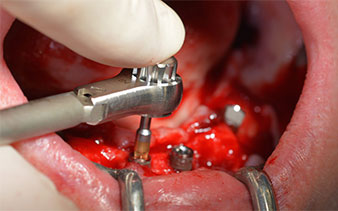

High primary stability is an absolute requirement for an immediate restoration. In order to achieve this, the hole was not tapped in this case. The W&H Implantmed drill unit used here is equipped with a suitable special mode for this, which can also be directly selected and is indispensable for many indications. The final revolutions when placing the implants exceeded the value of 32 Ncm and were performed by hand. In such cases, we recommend utilizing the implants’ self-tapping function and twisting the implants backwards and forwards several times. This allows the implant to approach the final position gradually without exerting excessive pressure on the bone (Fig. 14).

Implants

Fig. 14

Angled abutments (35°) were screwed in to compensate for the divergence of the distal implants, with the result that the emergence profile of all implants was as perpendicular as possible to the bite plane. This is a prerequisite for occlusal placement of the provisional and subsequently the permanent denture (Fig. 15 and 16).

Fig. 15

Fig. 16